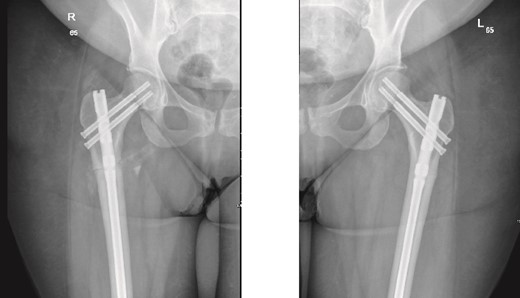

The patient was seen in the clinic at 2 weeks, 6 weeks, and 6 months post-surgery. She was doing well, reporting only mild pain. She was fully weight-bearing with the assistance of a cane and had good range of motion (Figs 3 and 4).

6-months follow-up anteroposterior (AP) view of the right and left femurs after CRIF with IM nail.

As part of the follow-up, the endocrinology team continued to monitor the patient for further investigation into the possible causes of the fractures. A BMD scan was performed and showed normal results. Based on their assessment, the endocrinology team diagnosed the patient with osteomalacia, most likely of nutritional origin.